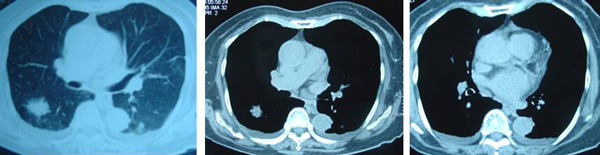

SH said she was well all these years and her progress was monitored by her doctor. About 10 years later, in early 2009, SH developed shortness of breath. She could not lift her left arm. She was tired and lost her appetite. A chest X-ray indicated large left pleural effusion. SH had the fluid in her lung tapped out. A CT scan on 7 January 2009 indicated several subcentimeter nodules in her left lung. The lymph nodes in the left axilla and aortopulmonary window were enlarged. Impression: left pulmonary and pleural metastasis.

SH sought a second opinion from another oncologist at a university hospital. Another CT scan was performed and it also confirmed a metastatic breast cancer with left pleural effusion with small benign liver cysts.

In August 2011 SH developed shortness of breath again. A CT scan on 4 August 2011 confirmed presence of mild left pleural effusion. Fluid was tapped out of her lung again.